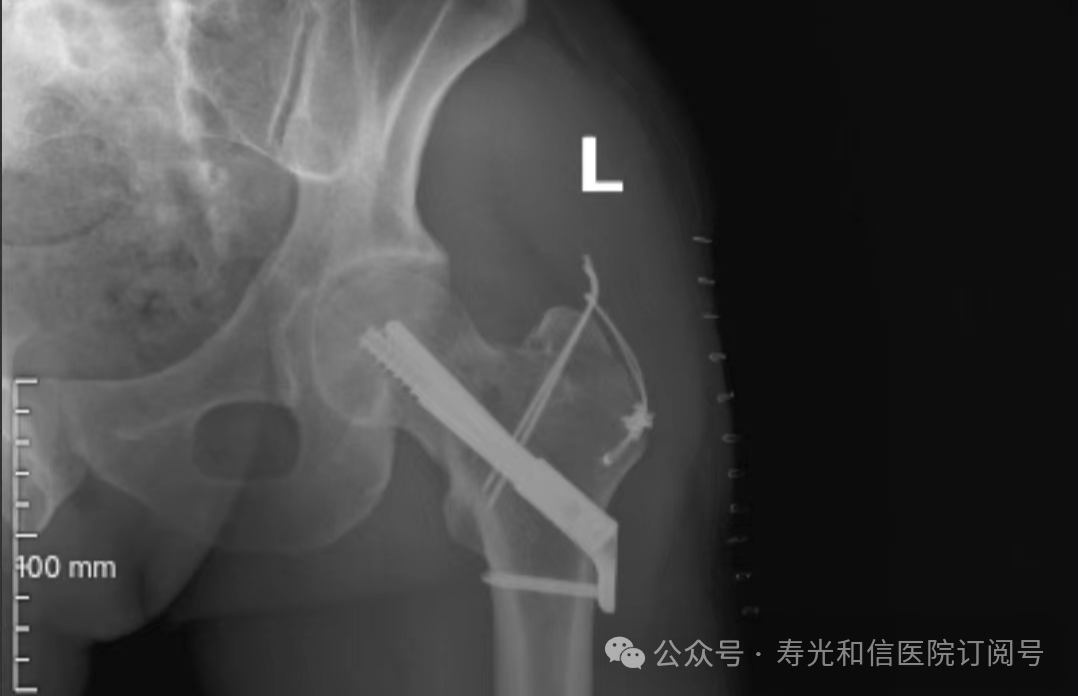

患者经120接诊,完善相关辅助检查后收入寿光和信医院骨外科。检查发现,患者右锁骨骨折、左股骨颈骨折、左大转子撕脱骨折、右膝关节前交叉韧带止点撕脱骨折、右膝关节外侧副韧带损伤、颅骨骨折及全身多处皮肤挫伤。因患者是外地来寿人员,家属短时间内不能赶过来,并且患者家庭经济条件较差,没有缴纳住院手术费的能力。但是股骨颈骨折后,股骨头坏死发生几率较高,手术越早进行,越有利于减少发生股骨头坏死的几率。骨外科主任李刚始终牢记救死扶伤的神圣职责,本着为病人负责的原则,坚定地选择先行为患者实行手术治疗。

与患者本人充分沟通后,李刚主任率领骨外科团队,经过充分的术前讨论及术前准备,于2024年9月1日为患者在全身麻醉下实施了4个半小时的内固定手术治疗。“时间就是生命”,手术过程中,全体参与人员密切观察病情变化,敏锐发现早期异常指标,争分夺秒,一丝不苟地做好各项抢救救治工作,做到瞬间判断、正确评估、果断处理,赢得了抢救患者的“黄金时机”,确保了手术的顺利完成。

在为其进行股骨颈骨折治疗时,手术团队为其采取了股骨颈动力交叉钉系统,这是一种新型股骨颈内固定系统,属微创植入,较从前的技术具有手术时间短、创伤小、力学稳定、滑动加压等优点。同时,患者恢复快,可早期离床、不负重下活动,缩短住院时间及康复时间,有效降低患者股骨颈骨折不愈合发生率,降低长期卧床合并症和死亡率。